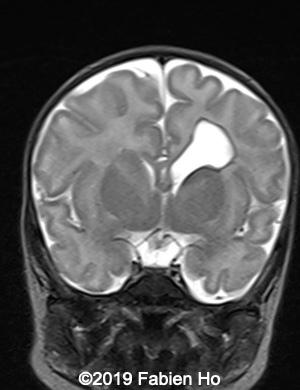

Images 1-3: in the left frontal lobe, hyperechoic with hypoechoic center lesion within the deep and periventricular white matter. Interestingly, this lesion has no mass effect on the lateral ventricle, and it has smooth margins.

Images 4-11, fetal brain MRI at 28 weeks: the left frontal lesion hence shows DWI hyperintensity, with T2* and T1 peripheral hyperintensity: ischemia with peripheral subacute hemorrhage. Note also that there is an associated blood clot in the left lateral ventricle. There is no obvious mass effect, nor peripheral edema. All these findin>gs are very suggestive of a clastic lesion.

Images 12-16: we performed a second fetal brain MRI at 32 weeks, which showed the same findings as the postnatal neonatal brain MRI as follows:

The evolution of the images is typical of a clastic lesion: after resorption of the ischemic tissue and hematoma, there was now a focal porencephaly with hemosiderin tattooing on its margins. Conversely, persistence of the same MRI findings would have indicated an hypercellular brain tumor, which could have been a differential diagnosis.